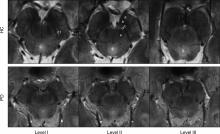

Research shows that ultra-high-field magnetic resonance imaging (MRI) provides detailed views of a brain area implicated in Parkinson’s disease, possibly leading to earlier detection of the condition. The results of this research are published online in the journal Radiology.